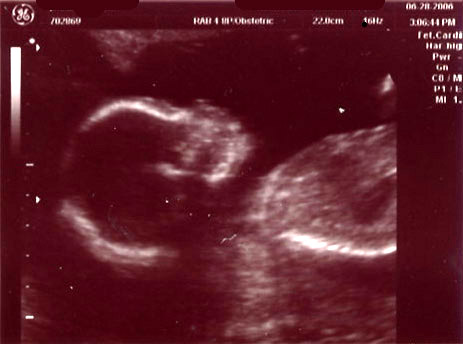

| June 28, 2006 - Twenty Week Ultrasound: IT'S A BOY!!! |

Today was probably the

longest day of my life having to wait for our 3:00pm appointment. I

went to work today, but didn't get much done since I was so excited to

finally find out what we were having. We got to the doctor's and they

took us right away. Within 44 seconds of the technician turning on the

ultrasound machine, she showed us the picture of the legs spread wide open

and it was obvious that we were having a boy!! He was so active

throughout the entire ultrasound, kicking and turning all over the place.

He is absolutely beautiful!!! I am in love with him already. He

weighed 13.5 ounces and he is perfect and healthy!! We are so excited

to start planning the nursery for our little man. Here are the

ultrasound pics from today. Enjoy!! ~Jen

View from the backside |

The boy parts :) |

Head shot of the little man |

More boy parts (just to be certain) |